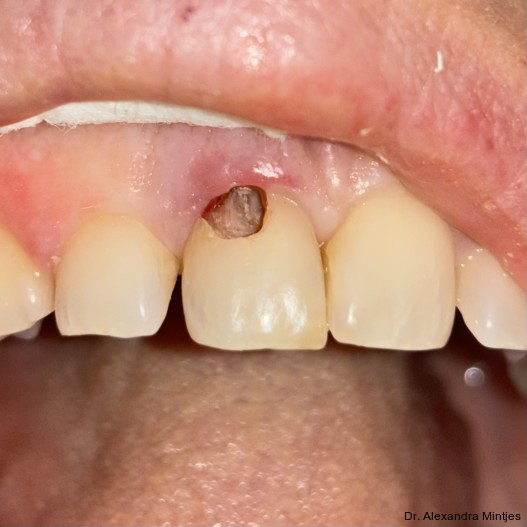

Bei der Erstvorstellung zeigte die vorhandene Füllung einen deutlichen Randspalt, war verfärbt und nach apikal hin insuffizient. Klinisch präsentierte sich ein dicker gingivaler Phänotyp mit ­harmonischer Weichgewebsbalance, jedoch bestand distal eine lokalisierte, entzündliche Zahnfleischtasche (Abb. 1). Es war zu vermuten, dass das nekrotische bzw. resorptive Hartgewebe nicht vollständig entfernt worden war. Auf dem DVT wurde das Ausmaß des Defekts deutlich. Zu­dem ließ sich eine deutliche apikale Aufhel­lung nachweisen, die Patientin war jedoch beschwerdefrei (Abb. 2).

Die Diagnose lautete eine invasive zervikale Resorption Klasse 3 nach Heithersay. Dieses Sta­-dium beschreibt eine tiefe Resorption mit Ausdehnung in das koronale Dentin und das zervikale Drittel der Wurzel, ohne dass die Pulpa vollstän­dig involviert ist. Solche Läsionen gelten als prognostisch kritisch und führen in der Regel zu einer extraktiven Therapie.